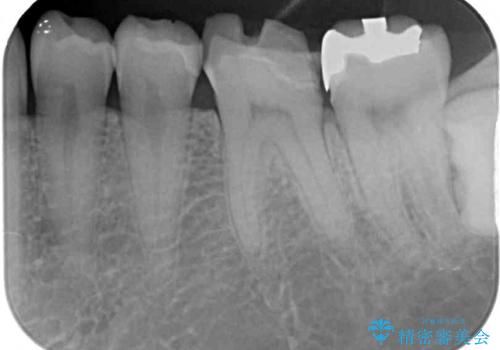

奥歯は虫歯が放置されていましたが、特に症状はなく歯髄の状態も正常でした。

前歯、奥歯ともにオールセラミッククラウンやセラミックインレーにて治療を行うこととしました。